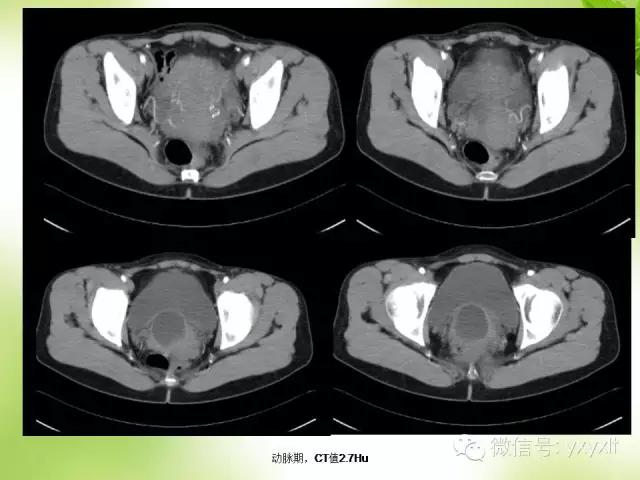

CT:囊肿表现为单房或多房的薄壁水样低密度病灶薄壁囊性肿块,边缘清楚光整。增强扫描未见强化。